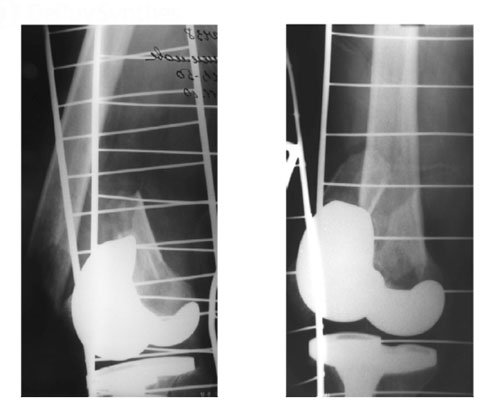

- Открытый оскольчатый перипротезный перелом правого бедра

Открытый оскольчатый перипротезный перелом правого бедра